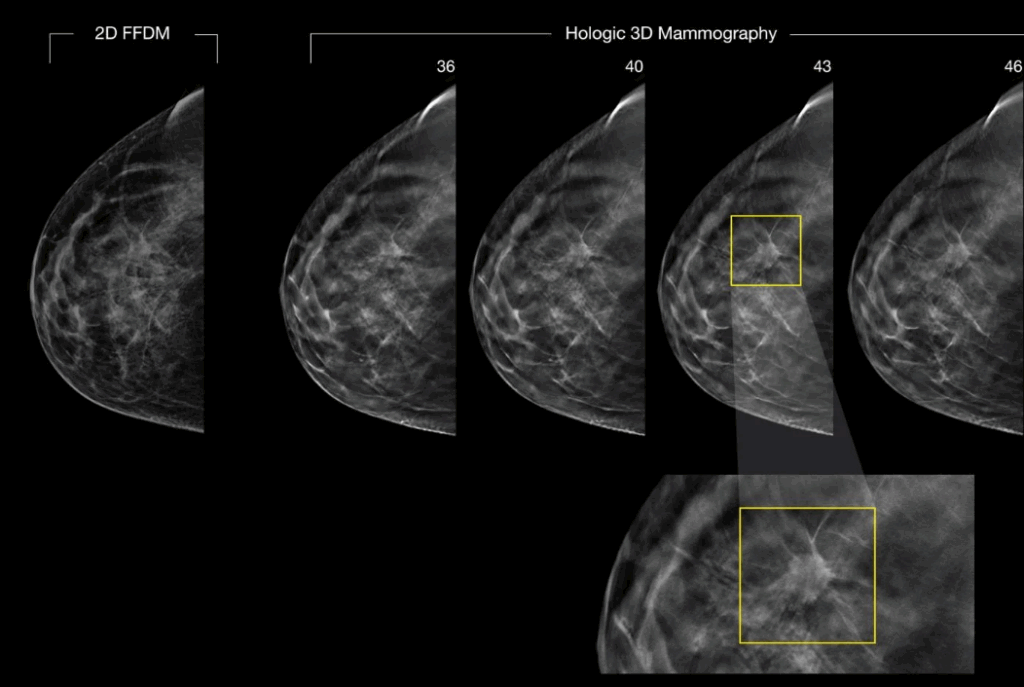

Mammography

img01

DBT (Digital Breast Tomosynthesis)

• More Accurate Breast Screening

3D mammography captures the breast from multiple angles and reconstructs it into a detailed 3D image. This helps doctors see through overlapping tissue and detect abnormalities earlier.

• Clearer Results, Fewer Callbacks

High-resolution images with strong contrast make it easier to find small lesions reducing the chance of needing repeat scans.

• Better Detection in Dense Breasts

3D mammography is especially helpful for women with dense breast tissue, where traditional 2D scans may miss small findings.

• Safer, Lower Radiation 2D Images

Our system uses Synthesized 2D, meaning it creates the 2D image directly from the 3D scan — no extra exposure and no second compression.

• Accurate Localization for Your Doctor

The 3D view provides exact information on the size, shape, and location of any lesion, helping your doctor plan the right care.